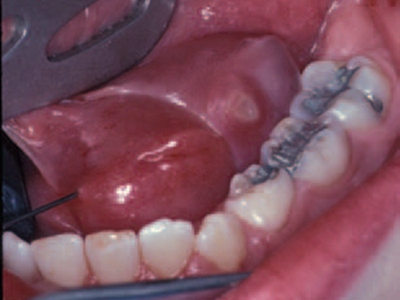

舌下腺囊肿舌头底下的筋旁边长个球形疙瘩图

舌下腺囊肿位于舌系带一侧的口底黏膜下,表现为表面光滑的球状大疙瘩,常继发感染导致局部肿胀、疼痛,呈进行性增大,并越过舌系带在对侧隆起。